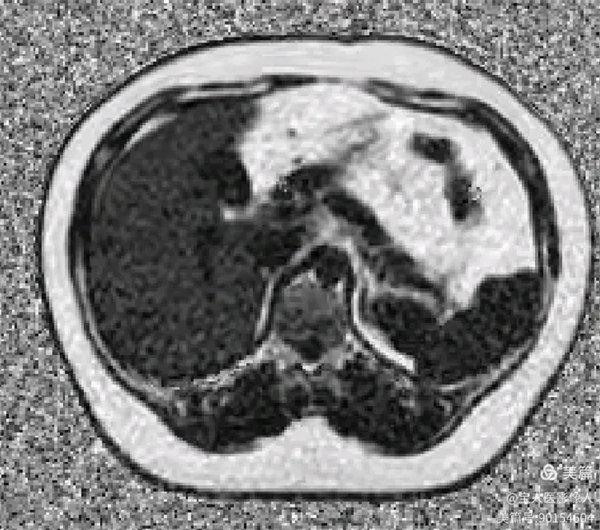

圖5

FatFrac圖(脂肪分量圖)肝實質信號均勻性升高。

圖6

PDFF測值,測量全肝實質多部位的脂肪分數值12%—17%,提示:脂肪肝,MR-PDFF,二級,中度。